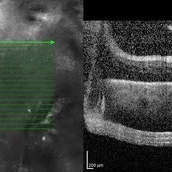

Best Disease Best DiseaseMar 9 2013 by Hamid Ahmadieh, MD OCT of the right eye of a 49-year-old man with decreased VA due to advanced Best disease. Photographer: Soodabeh Fooladin, Negah Eye Center, Tehran Imaging device: Heidelberg Spectralis Condition/keywords: Best disease, optical coherence tomography (OCT)